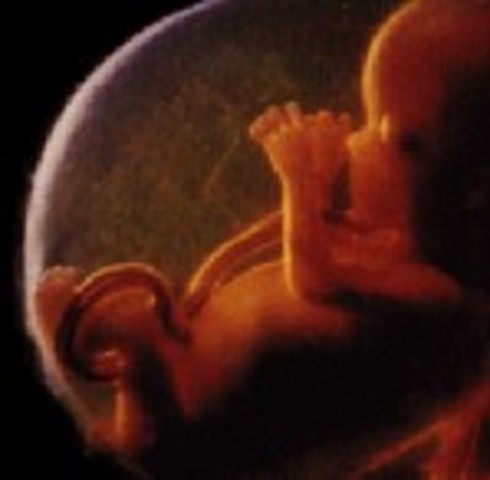

• Week 20: Half way

Week 20: Half way

The baby is 7 inches long and weighs 11 ounces. The baby can now hear voices or loud sounds during development which will become recognizable once he or she is born. Hair growth is developing on the rest of the body, skin is thick, and the heart can be heard.

Facts: -If born, baby could survive

-Babies are measured from the crown of the head to the bottom